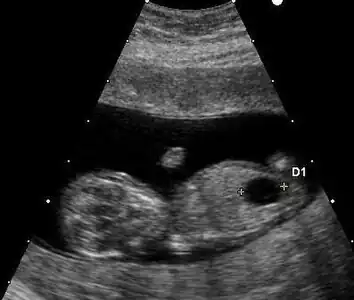

Ultrasound

Ultrasound imaging can be used to screen for Down syndrome. Findings that indicate increased risk when seen at 14 to 24 weeks of gestation include a small or no nasal bone, large ventricles, nuchal fold thickness, and an abnormal right subclavian artery, among others.[89] The presence or absence of many markers is more accurate.[89] Increased fetal nuchal translucency (NT) indicates an increased risk of Down syndrome picking up 75–80% of cases and being falsely positive in 6%.[90]